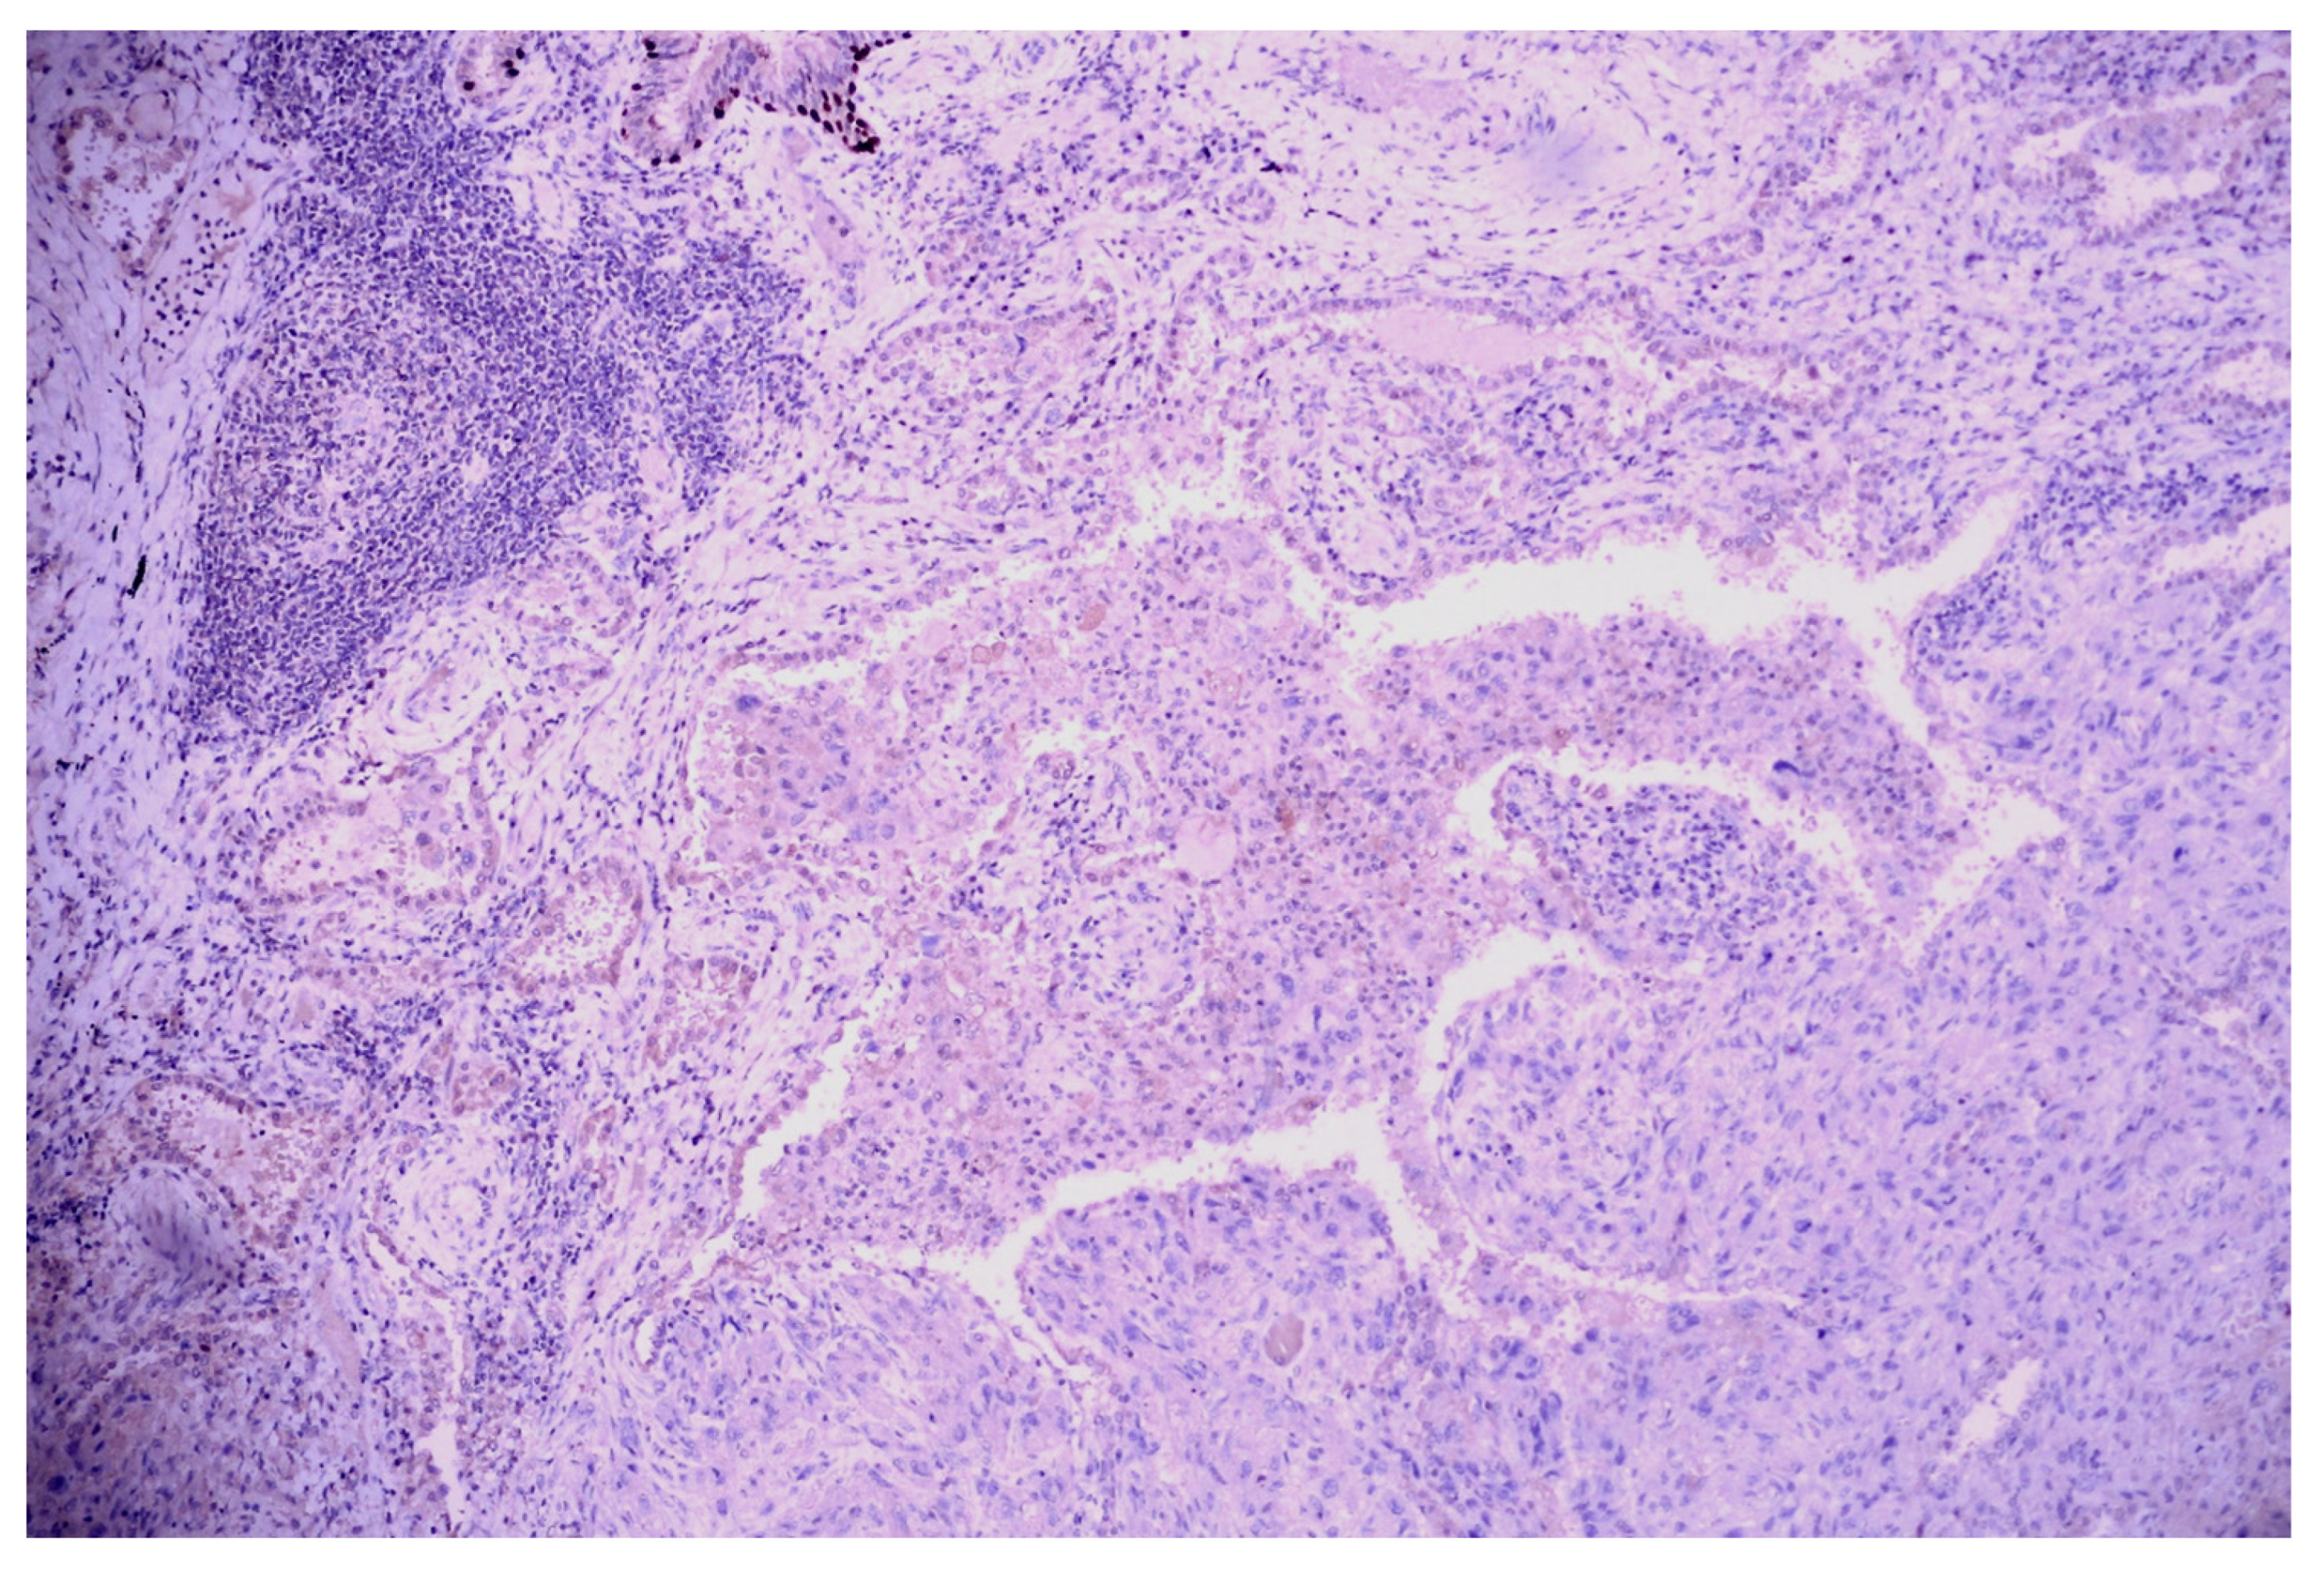

3.1. Case No. 1

3.2. Case No. 2

3.3. Case No. 3

3.4. Case No. 4